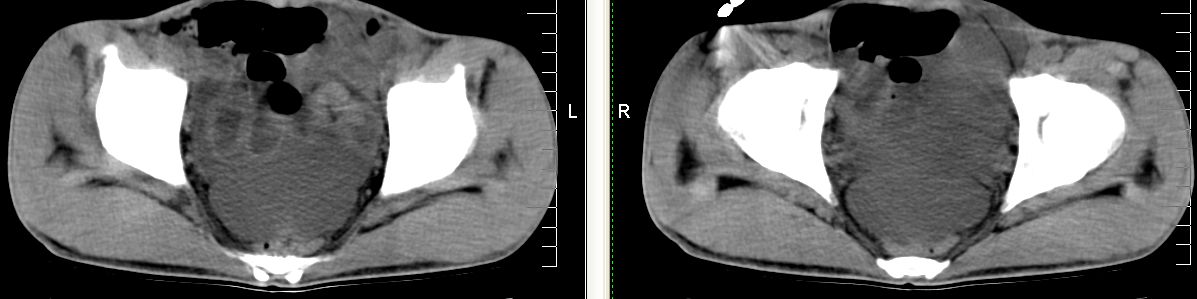

m 29 肺tb患者,目前诉下腹疼痛 t39度 腹韧,有压痛,可触及3x4cm包块

脾脏多发低密度灶,肠系膜及腹膜后见多发大小不等结节状影,右结肠旁沟见低密度影,结合病史考虑:脾结核,肠系膜及腹膜后淋巴结结核,少量腹水。

右侧结肠亦可见病变,腹膜后可见多发增大的淋巴结影,脾脏内示多个低密度结节灶,结合病史考虑结核性病变。

脾脏多发低密度灶,腹膜后及肠系膜根部多发淋巴结淋巴结肿大并部分相互融合,考虑tb.图象窗宽\\窗位没调整好,不清晰,另外,肠道准备亦不理想.

脾脏多发低密度灶,左侧肾上腺见块状病灶,密度不均,盲肠升结肠肠壁明显增厚,左下腹似可见肠壁增厚,肠系膜及腹膜后见多发大小不等结节状影,右结肠旁沟见低密度影,1淋巴瘤可能大,2结合病史考虑:脾结核,左侧肾上腺结核,肠系膜及腹膜后淋巴结结核,少量腹水待除外,